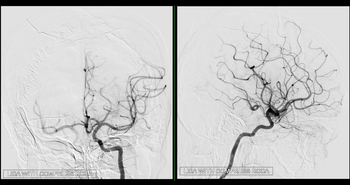

• Thrombectomie

Plus de 180 thrombectomies réalisées en 2025 : une progression qui confirme la force du travail en r

Une collaboration fructueuse et durable entre le Pr Boris Lubicz et le service de Radiologie